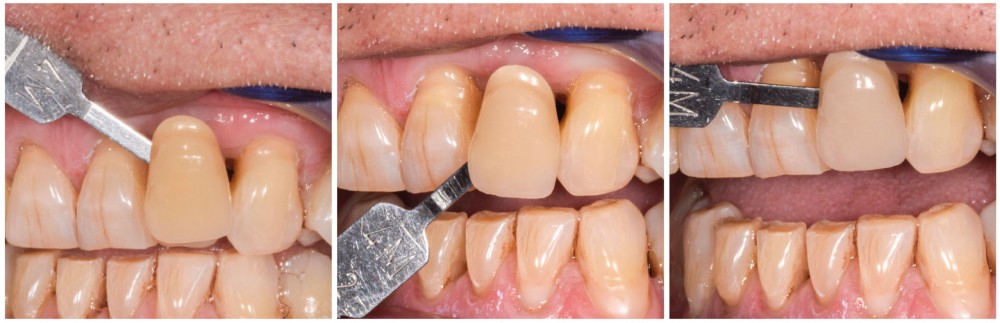

Au vu des conditions initiales, il nous apparaît impossible de restaurer une esthétique satisfaisante, notamment au niveau de l’alignement des collets, sans une chirurgie muco-gingivale associée à une réhabilitation des dents antérieures par facettes. En effet, la perte de la 22, associée à une forme triangulaire des dents, a provoqué un non-alignement des collets ainsi que la présence de trous noirs entre les dents 21-22 et 22-23. Cependant, les contraintes exprimées par le patient contre-indiquaient ce traitement.

La proposition thérapeutique retenue par le patient est donc une réhabilitation par couronne céramique sur 12 (dento-portée) et 22 (implanto-portée). Ce choix thérapeutique impose de concevoir des dents qui s’intègrent au mieux dans l’harmonie du sourire, tout en étant conscient des limites d’un tel traitement.